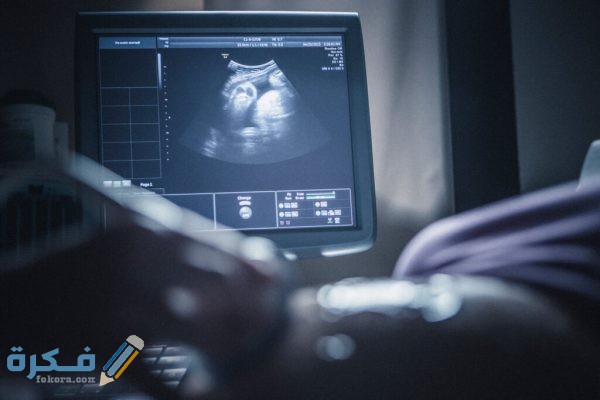

أكمل القراءة »كيف يحدد الرجل نوع الجنين عبر موقع فكرة، أثبتت الدراسات العلمية ان الرجل هو المسئول عن تحديد نوع الجنين سواء ذكر…

أكمل القراءة »كيف يحدد الطبيب موعد الولادة عبر موقع فكرة، بمجرد ما تتوجه الحامل للمتابعة مع الطبيب المختص سيقوم بتحديد موعد تقريبي للولادة…